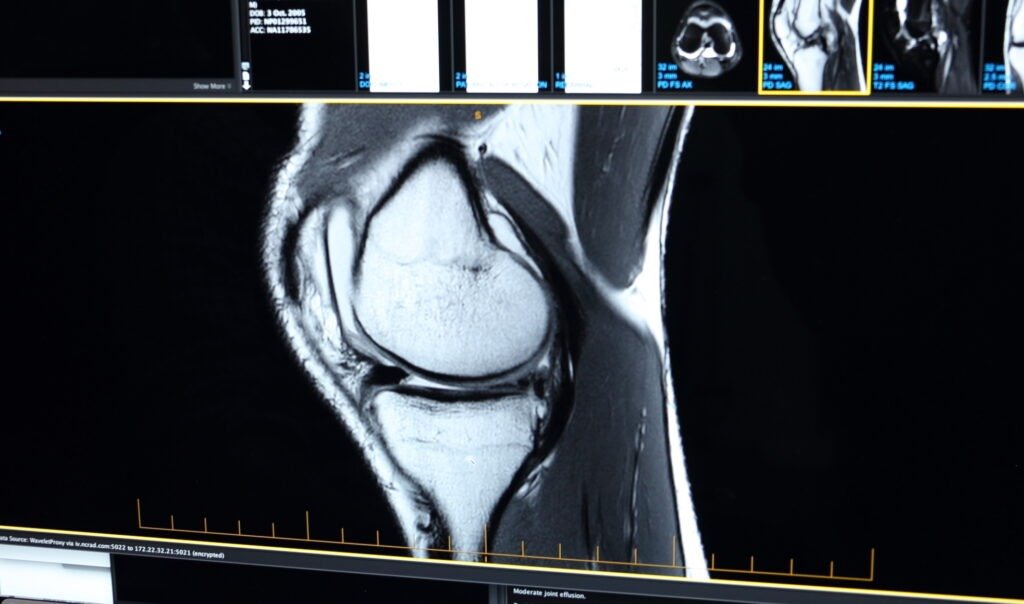

- X-rays to assess joint space, bone alignment, and signs of arthritis

- MRI scans to evaluate soft tissue structures such as cartilage, menisci, ligaments, and tendons